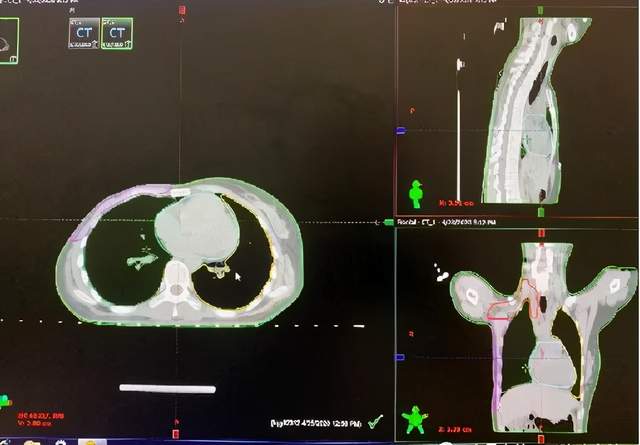

乳腺癌术后辅助放疗

保乳术后放疗

股骨头转移放疗

小细胞肺癌放疗